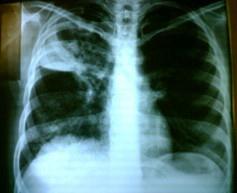

问题 男,55岁,有肺结核史,近1个月来咳嗽、低热,痰中带血,X线胸片如图所示: 若该病人确诊为肺癌,对预后影响最大的因素是 ( )

选项 A、已发现纵隔转移 B、出现骨关节病综合征 C、属中央型肺癌 D、属小细胞肺癌 E、肿块巨大

答案 D